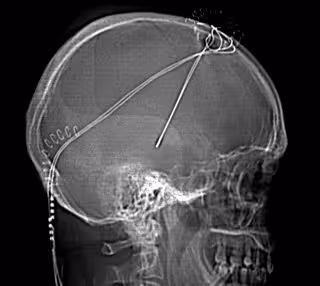

Tratamiento Parkinson

HOSPITAL BELLVITGE